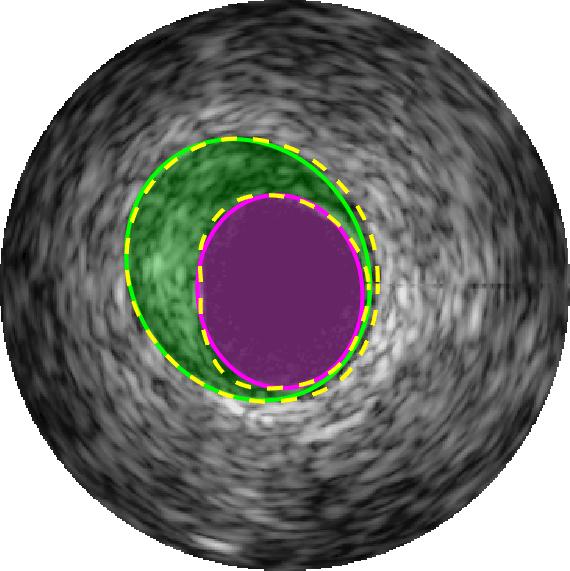

Qualitative evaluations are illustrated in Figure 4 and show the successful segmentation results of the proposed EREL selection strategy for 20 IVUS frames. The lumen areas are highlighted by the magenta colour while the media regions are green. Also, the manually annotated contours for both lumen and media are drawn as yellow dashed lines. As we can see, the chosen frames contain a variety of lumen and media morphologies.